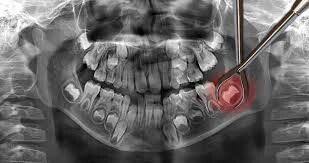

Impacted wisdom teeth hardly ever erupt

Not all wisdom teeth make it out of the gums. Some get impacted, meaning they are trapped in the jawbone or blocked by other teeth. This often happens when the wisdom teeth come in at an awkward angle. Impacted wisdom teeth can cause severe pain and will need to be removed through a surgical procedure.

Wisdom teeth extraction is not as painful as you thought